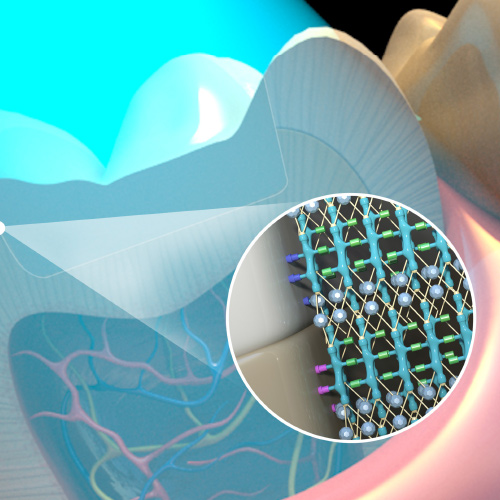

Digital Imaging Advances

This Compendium eBook offers a continuing education (CE) article on CAD/CAM custom-made titanium meshes to facilitate guided bone regeneration. This article includes two case studies of patients with severe ridge atrophy for whom CBCT and CAD/CAM were used to design titanium meshes for ridg...

Bioactive Dental Materials: The Future Is Now

Wednesday, July 28, 2021

This Compendium eBook features a continuing education (CE) article that describes how the recent development of bioactive dental materials has increased the longevity of dental restorations and improved clinical outcomes after dental procedures.